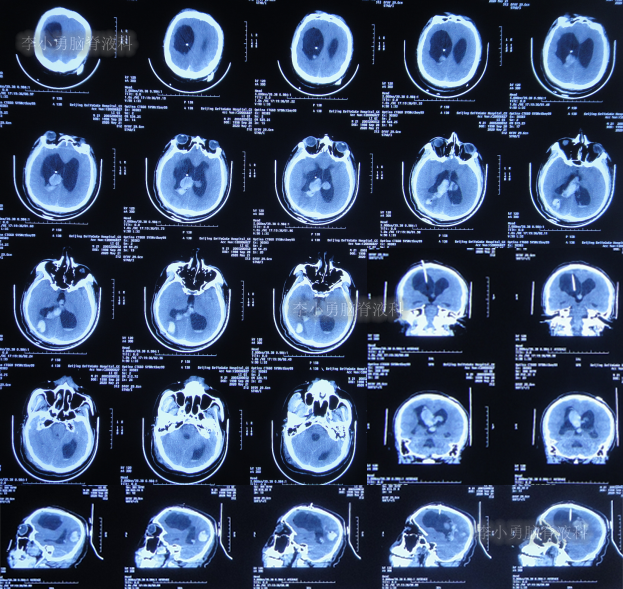

发现脑积水15年后即2020年1月份,开始出现头胀头闷能自行缓解,并没有特殊处理,3月后即2020年4月8日,因症状变重且变频繁,至甘肃省天水市某医院检查头颅核磁(图-3)认为脑积水较前(2016年7月20日头颅CT)加重。

图-3:2020年4月8日头颅核磁

1个月后即2020年5月6日,为治疗脑积水,至陕西省西安市某三甲医院就诊,查头颅核磁示脑积水(图-4)。

图-4:2020年5月6日头颅核磁